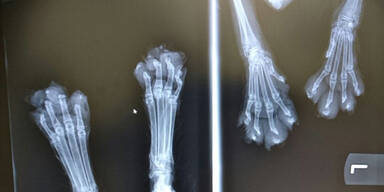

Die Pfoten des Tiers sind stark entzündet und eitrig.

Mittels Röntgen konnte in der Tierklinik das Ausmaß der Verletzungen festgestellt werden: Der Katze wurden tatsächlich sämtliche Zehen abgeschnitten. Die Untersuchung ergab, dass die Verstümmelungen schon zwei bis drei Wochen unbehandelt sind.